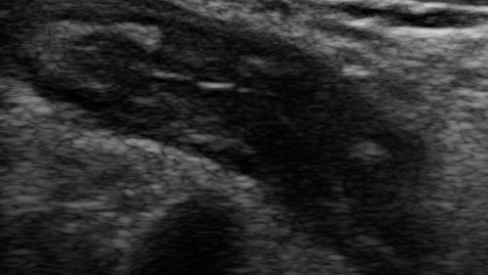

Острый аппендицит (УЗИ). Подборка случаев.